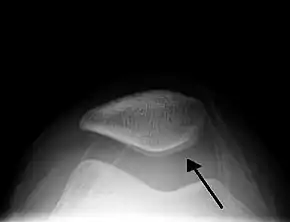

| A traumatic right knee effusion. Note the swelling lateral to the kneecap as marked by the arrow. | |

Skyline view of the patella demonstrating a large joint effusion as marked by the arrow.